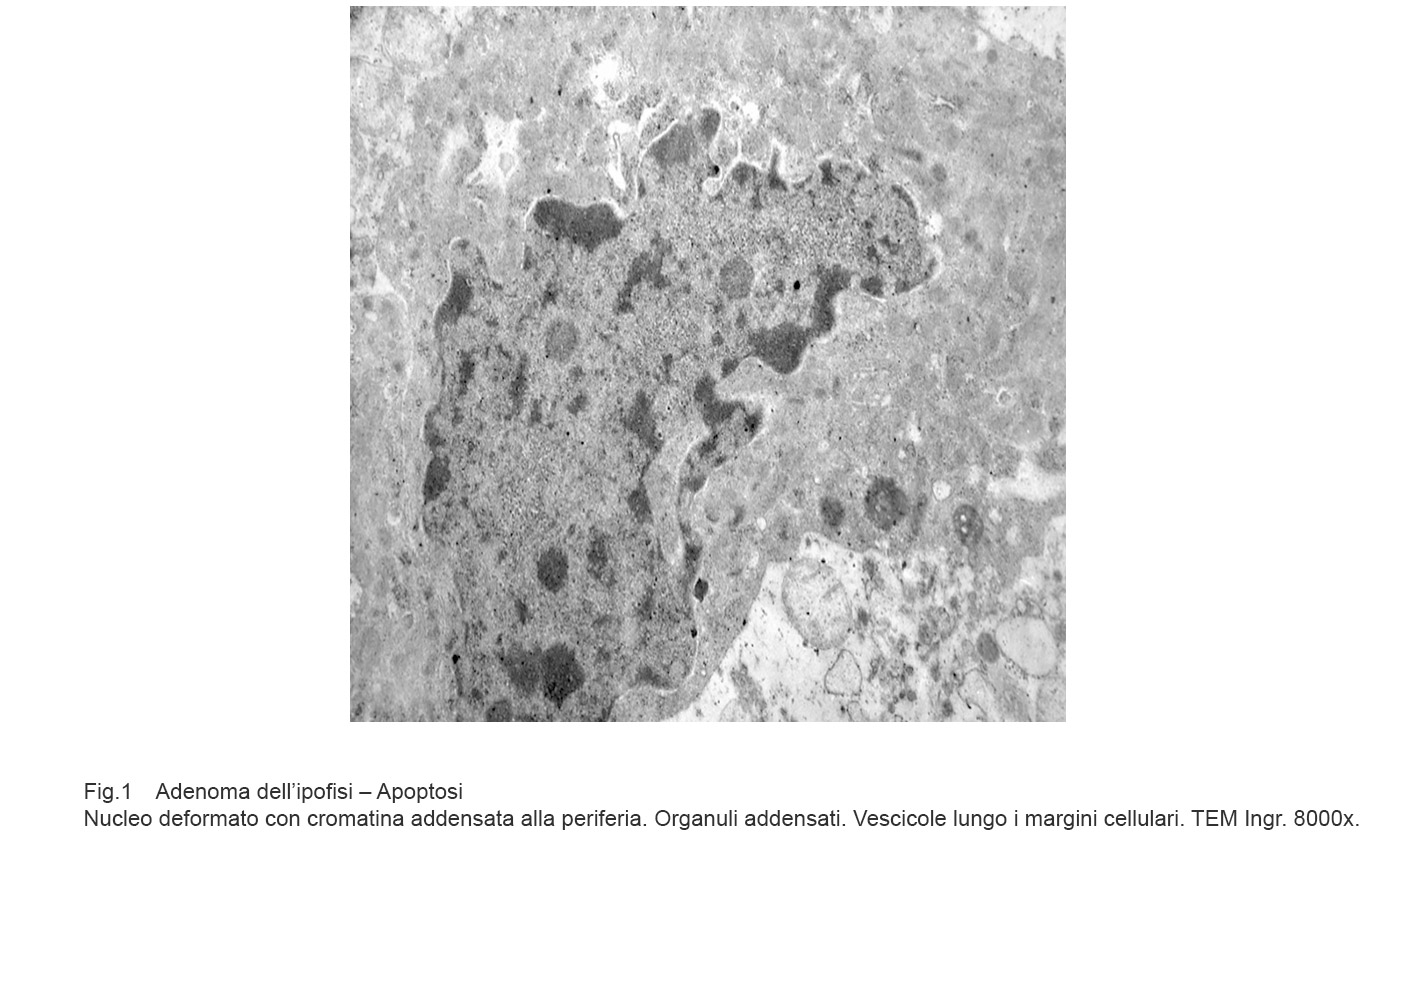

La morfologia delle cellule apoptotiche è ben caratterizzata. Esse si riducono di volume, acquistano una forma sferoidale e perdono i contatti con gli elementi cellulari .

Questi cambiamenti morfologici sono correlati alla frammentazione del citoscheletro e alle alterazioni del nucleo che appare picnotico con blocchi di cromatina marginati a ridosso della membrana nucleare.

Gli organuli citoplasmatici sono sostanzialmente conservati, mentre sulla superficie della cellula si formano vescicole.

Fig.1